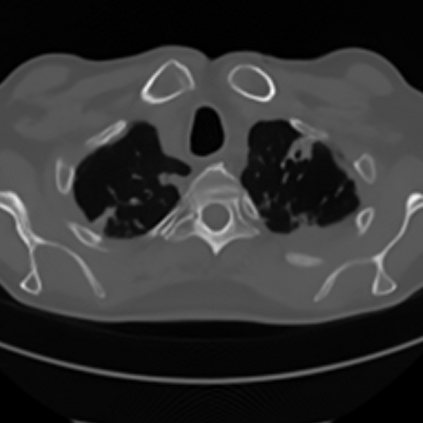

Sparse-view computed tomography (CT) -- using a small number of projections for tomographic reconstruction -- enables much lower radiation dose to patients and accelerated data acquisition. The reconstructed images, however, suffer from strong artifacts, greatly limiting their diagnostic value. Current trends for sparse-view CT turn to the raw data for better information recovery. The resultant dual-domain methods, nonetheless, suffer from secondary artifacts, especially in ultra-sparse view scenarios, and their generalization to other scanners/protocols is greatly limited. A crucial question arises: have the image post-processing methods reached the limit? Our answer is not yet. In this paper, we stick to image post-processing methods due to great flexibility and propose global representation (GloRe) distillation framework for sparse-view CT, termed GloReDi. First, we propose to learn GloRe with Fourier convolution, so each element in GloRe has an image-wide receptive field. Second, unlike methods that only use the full-view images for supervision, we propose to distill GloRe from intermediate-view reconstructed images that are readily available but not explored in previous literature. The success of GloRe distillation is attributed to two key components: representation directional distillation to align the GloRe directions, and band-pass-specific contrastive distillation to gain clinically important details. Extensive experiments demonstrate the superiority of the proposed GloReDi over the state-of-the-art methods, including dual-domain ones. The source code is available at https://github.com/longzilicart/GloReDi.